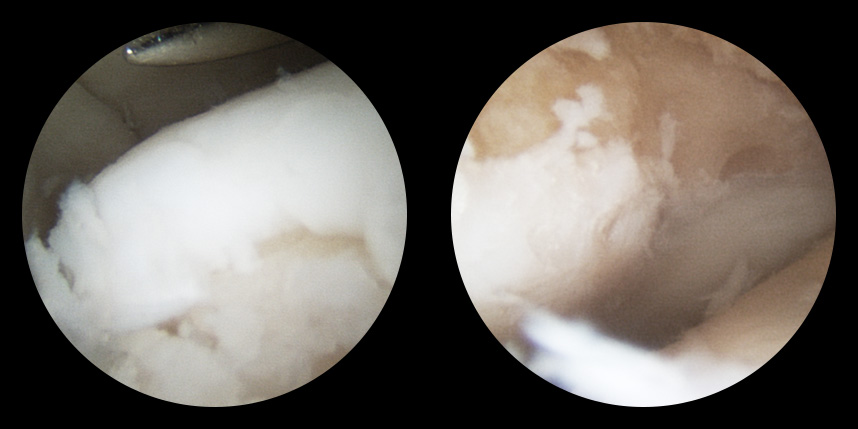

연골재생술 진행

(미세천공술 + alpha)

타병원 미세천공술 실패 후 통증으로 내원하신 사례

* 환자에게 받은 소중한 자료입니다.